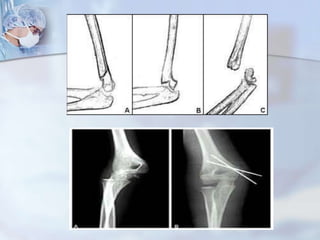

 CUBITO VARO(fractura supracondilea)

 CUBITO VALGO(fractura epicondilo medial)

 ADQUIRIDA:  POSTRAUMATICA CUBITO VARO(fractura supracondilea)  CUBITO VALGO(fractura epicondilo medial)  ARTRITIS REUMATOIDE  CODO DE ESTUDIANTE(Bursitis olecranon)  CODO DE MINERO(Bursitis olecranon)